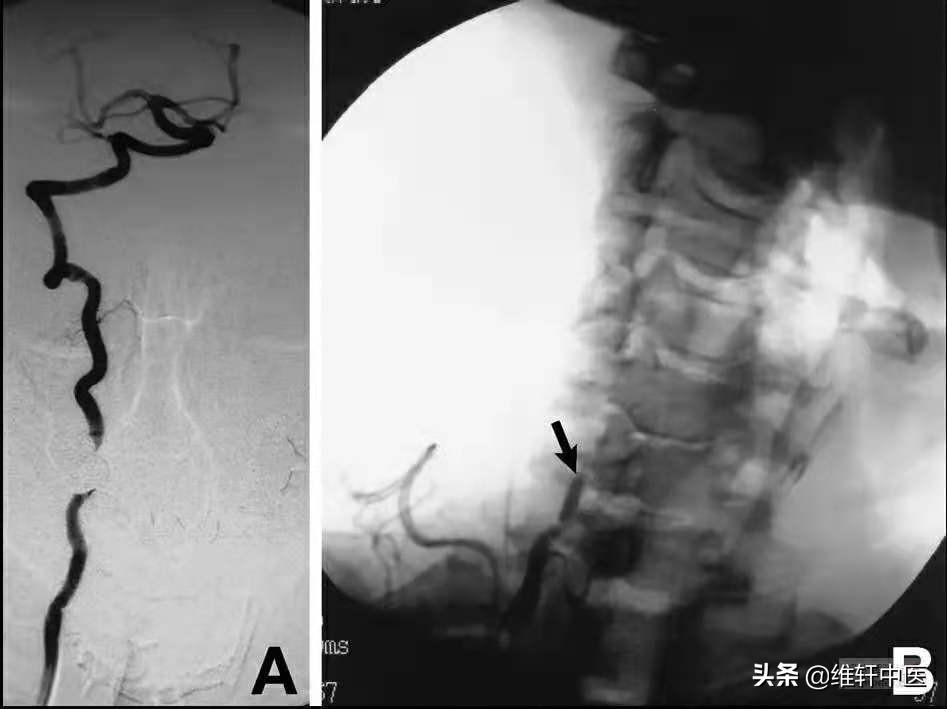

动态右侧椎动脉DSA: A:头正中位,血流正常(牙齿伪影), B:头向左侧转动,C6水平右侧VA完全闭塞,文献。